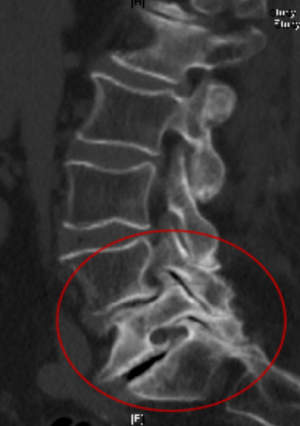

核磁检查可见骨质增生,椎间孔狭窄,椎间隙变窄由于患者年龄大,两年前曾接受过微创手术及后路开放手术各1次,局部解剖结构发生改变,椎管内瘢痕组织形成,神经根粘连严重,责任痛点难以确认,再次手术相当于对腰椎进行第三次“翻修”,难度极大。